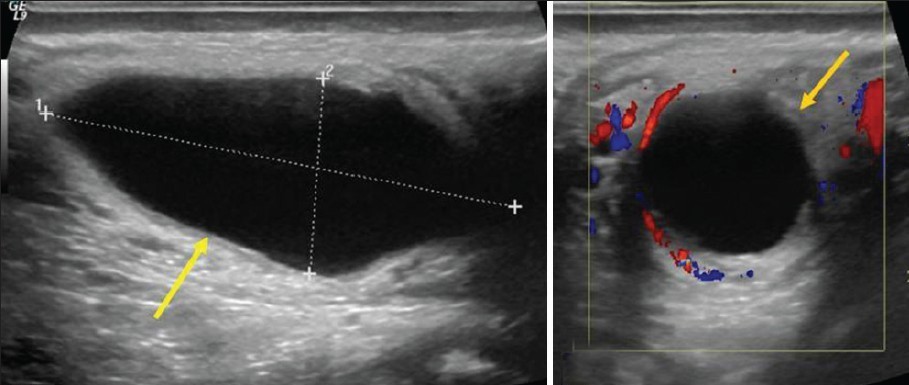

На УЗИ гематома меж оболочек мошонки в острый период выглядит как почти анэхогенное образование, часто с неровным контуром, заключенное между мясистой и влагалищной оболочками мошонки. Со временем содержимое становится неоднородным за счет появления нитей фибрина и сгустков в виде перегородок. В процессе организации гематома уменьшается и из ее содержимого исчезает жидкостной компонент, а на УЗИ в месте травмы визуализируется объемное образование неравномерно повышенной эхогенности, часто с кальцификатами. В случае нагноения гематомы образуется абсцесс.

Фото. Мужчина 25-ти лет получил прямой удар в пах во время занятий спортом. На УЗИ стенка мошонки утолщена, меж оболочек мошонки почти анэхогенное бессосудистое образование (стрелка). Диагноз: Гематома мошонки (острый период).

Фото. «Созревая» гематома мошонки теряет жидкостный компонент и становится неравномерно гиперэхогенной (стрелка).